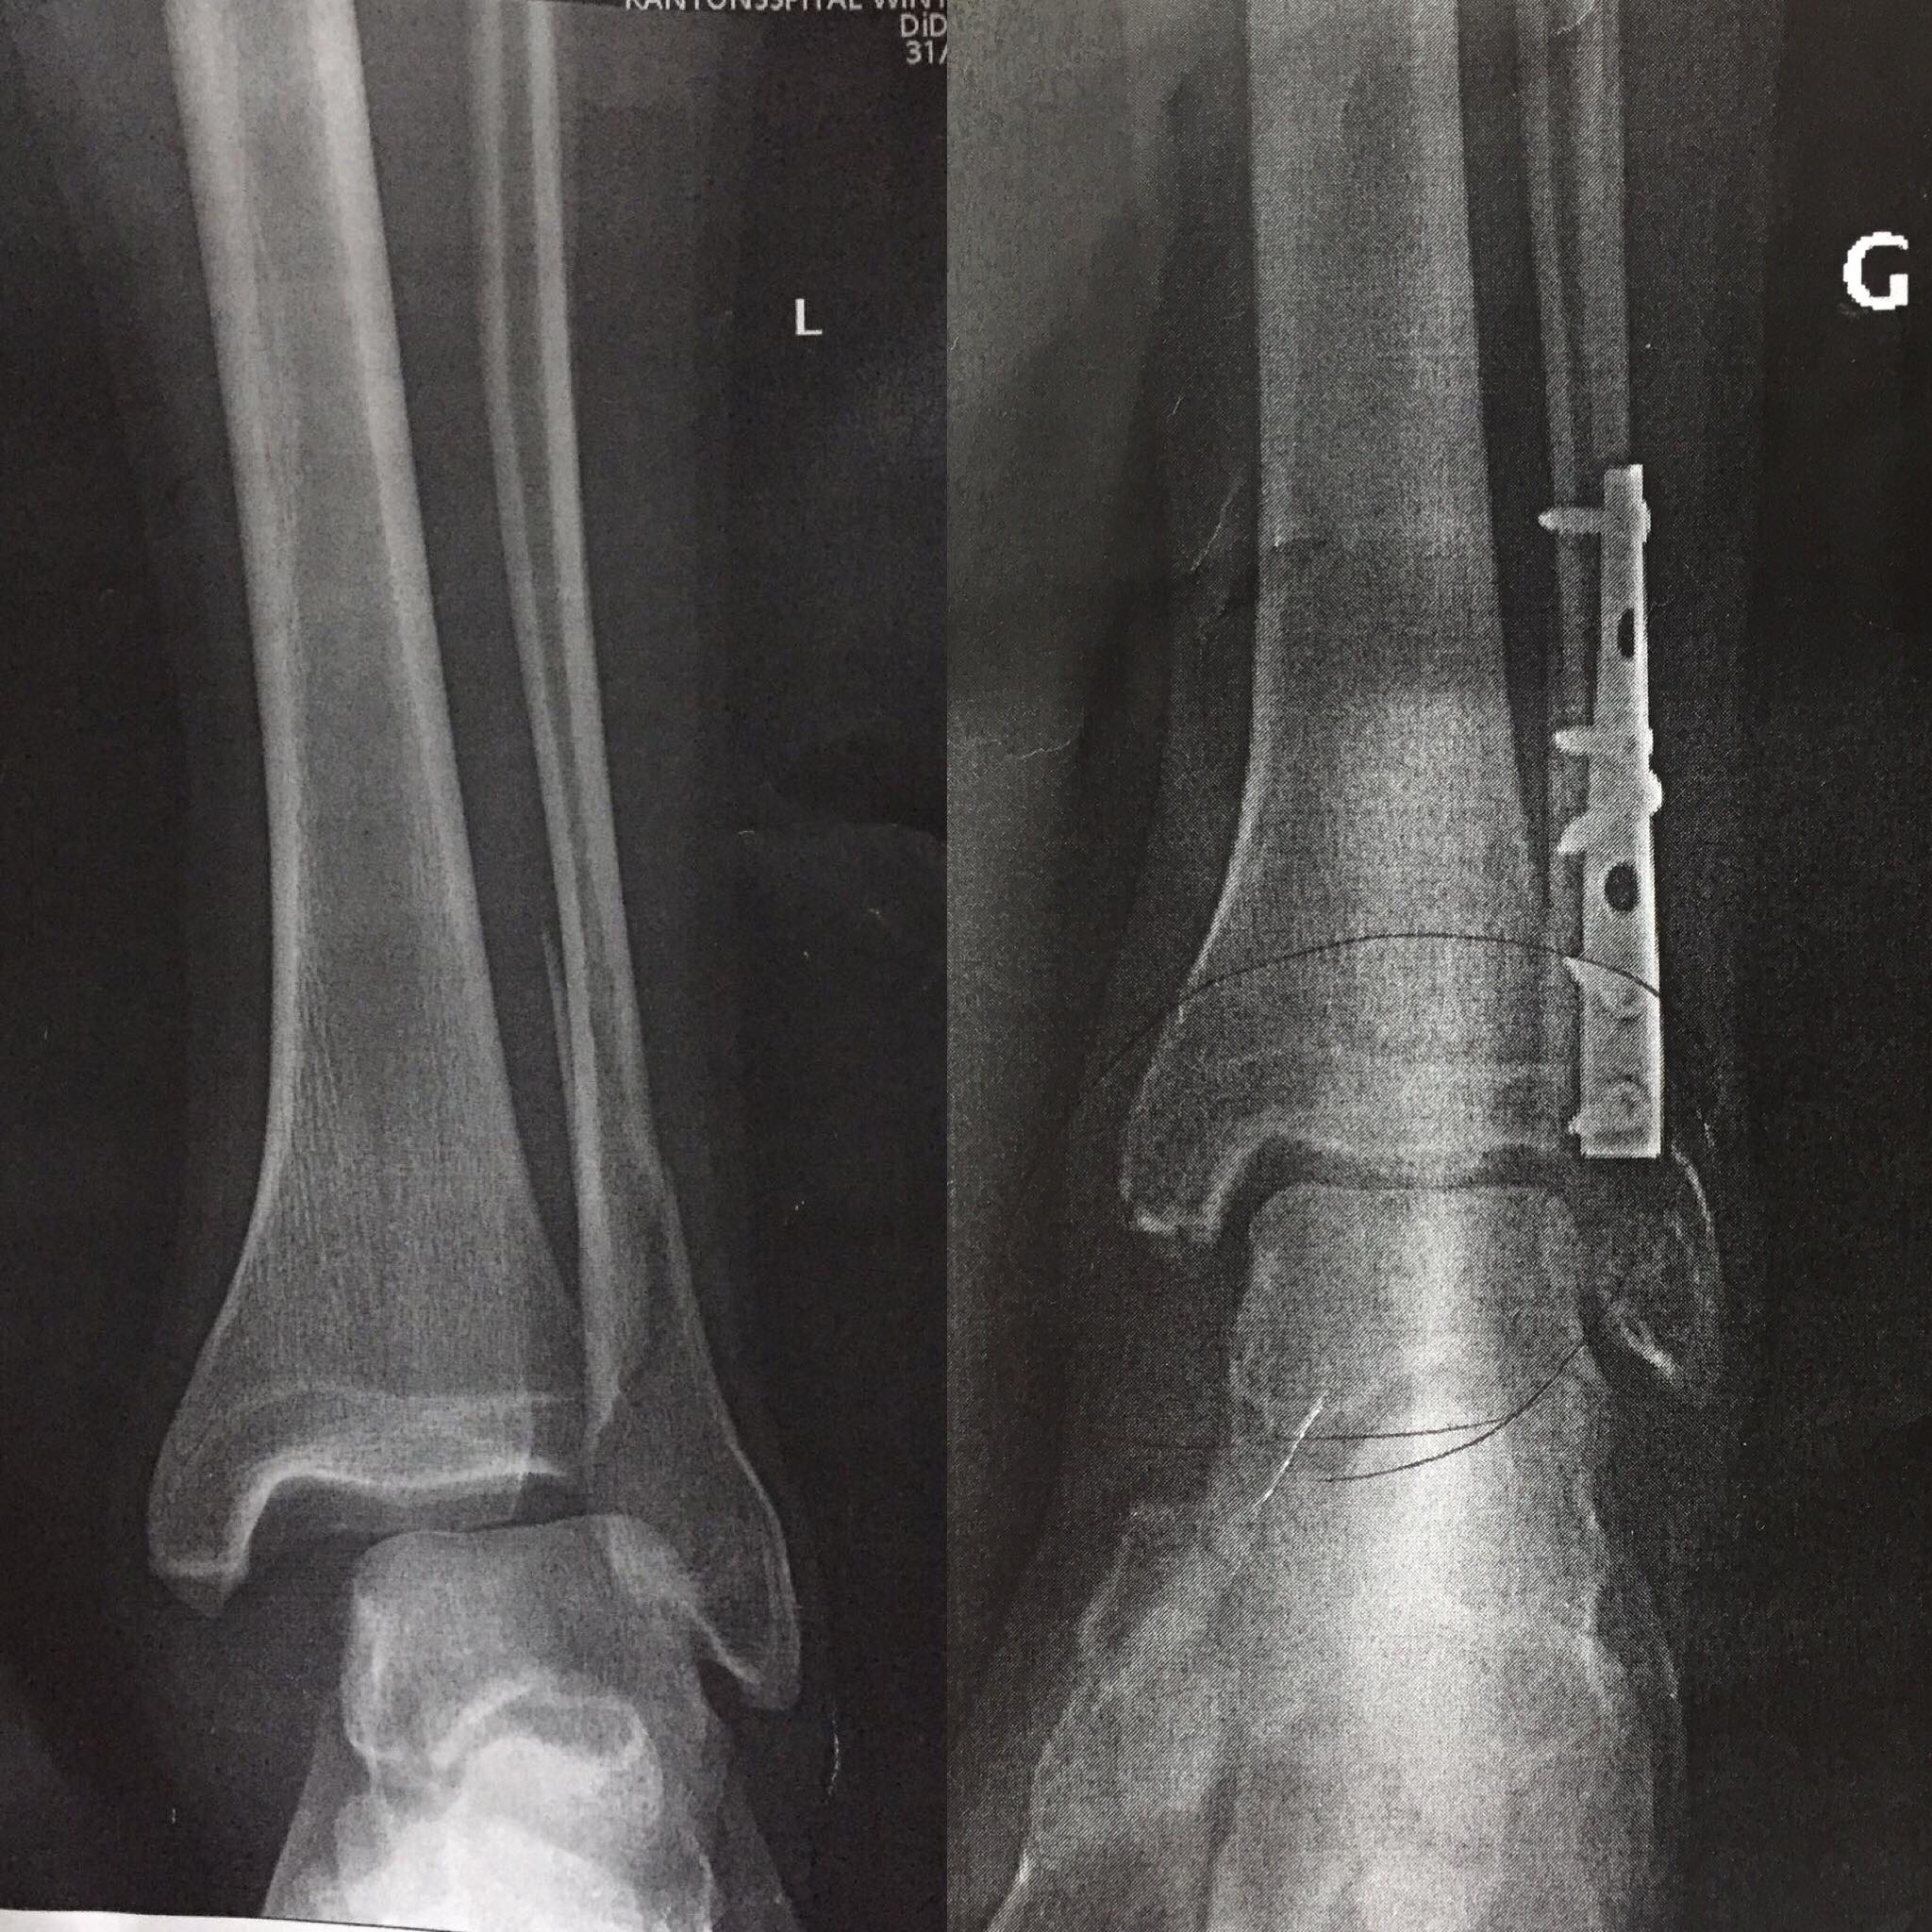

A seulement 23 ans, Thomas Genon a déjà presque 10 ans de carrière derrière lui. Vainqueur du classement général du FMB World Tour en 2015 avec plusieurs victoires sur des épreuves Diamond et Gold à son actif, ainsi qu’une 5e et une 6e place à la Rampage en 2015 et 2016, le petit Belge, qu’on surnomme affectueusement « La Frite » dans le milieu, est passé du statut d’espoir de la discipline à celui de référence dont les runs propres et stylés sont la marque de fabrique. Lors d’un de ses passages en Belgique cet été, nous avions réalisé quelques clichés et mangé une… frite avec lui. Aujourd’hui, alors qu’il est en pleine convalescence après une mauvaise chute, nous en avons profité pour prendre un peu de son temps pour une interview. Rencontre.

Alors Thomas, on a fait une cabriole ? Qu’est-ce que tu t’es fait comme blessure et comment vas-tu ?